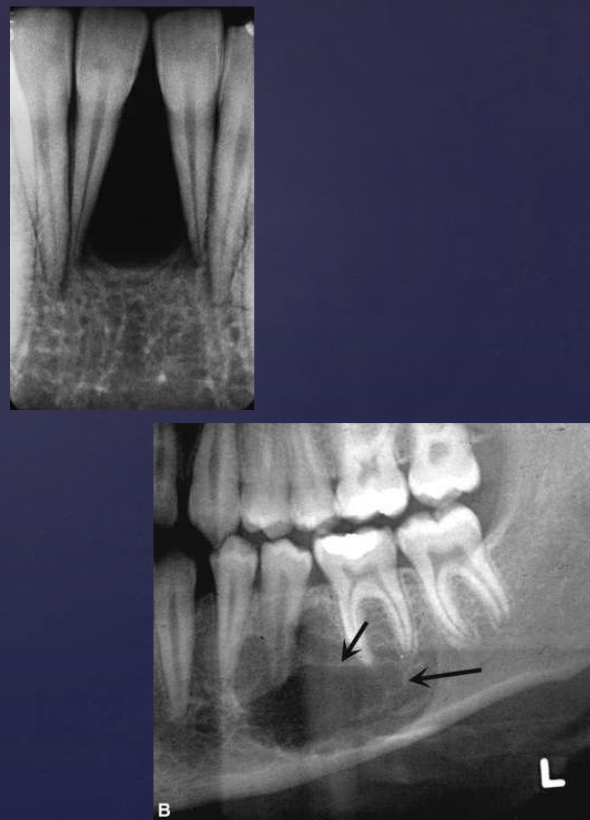

describe what’s occurring in this radiograph

pericoronal/mural; impacted tooth

displacement of #32 + IAN

osseous expansion

thinning of cortices

describe the ameloblastoma in this radiograph

multilocular w/ coarse septae

thinning of inferior mand border

displacement of teeth + IAN